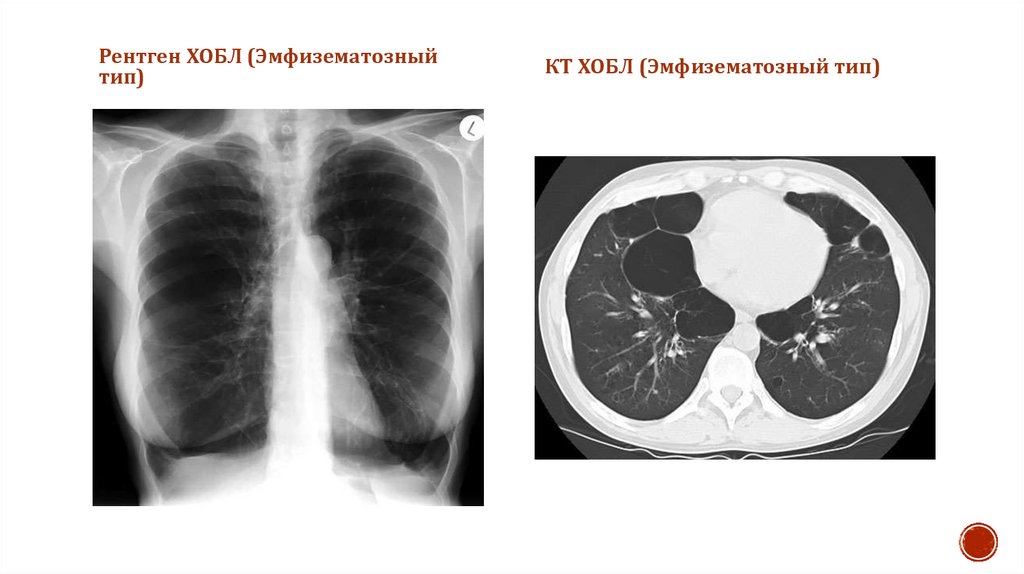

Рентген ХОБЛ (Эмфизематозный

тип)

КТ ХОБЛ (Эмфизематозный тип)

Эмфизематозный тип ХОБЛ

Бронхоскопическое исследование

Лечение хобл